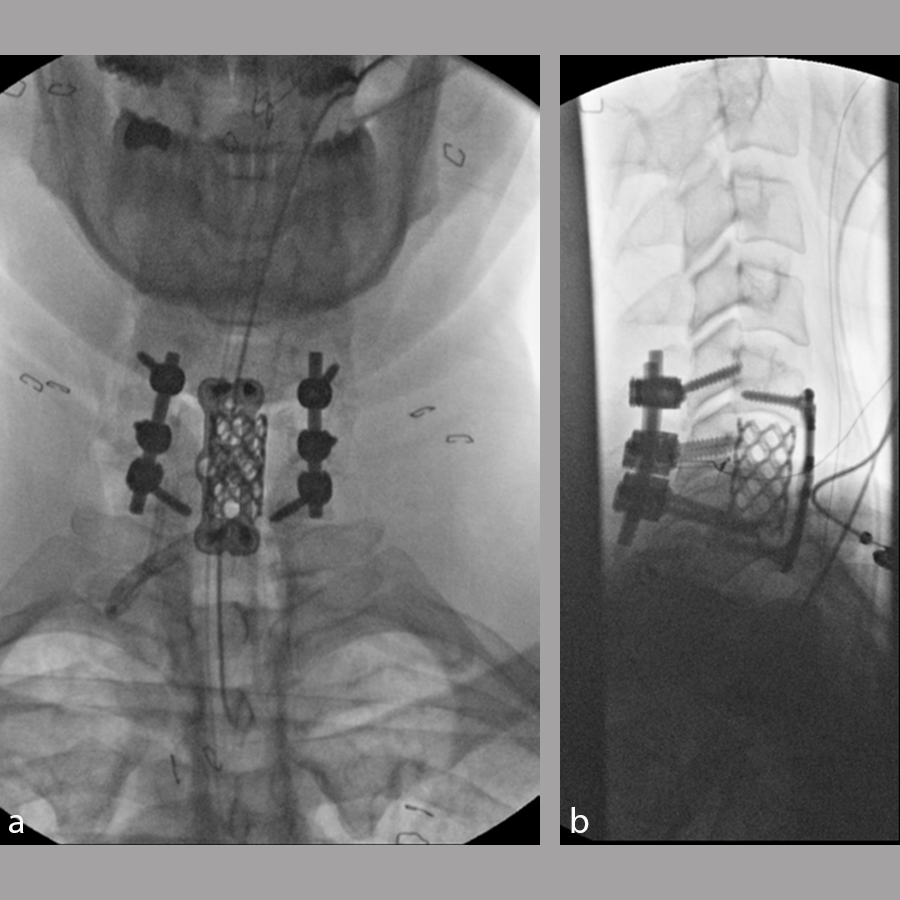

The patient underwent a C6 corpectomy with removal of fractured C6 vertebral body, restoration of height and placement of a Synmesh cage filled with autograft from the fracture. Following restoration of height and vertebral body reconstruction, a CODA™ ACP plate was applied anteriorly with screws into the C5 and C7 vertebral bodies. Given the psychosocial nature of the patient and the fracture pattern, the patient was then placed prone and underwent posterior instrumentation with Symphony instrumentation with lateral mass screws into C5 and C6 bilaterally and pedicle screws into C7 followed by placement of 4 mm rods along with fusion (Fig 11). The patient did well postsurgery (Fig 12) and was discharged according to protocol, but was unfortunately then lost to follow-up.